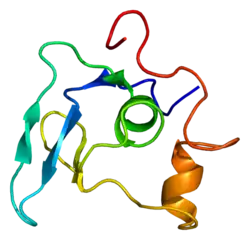

| A mutation in the protein profibrillin, encoded by FBN1, is the cause of Marfanoid–progeroid–lipodystrophy syndrome. | |